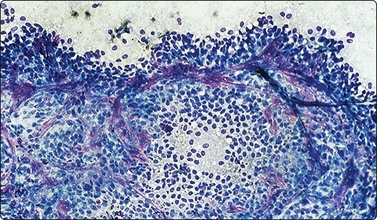

Neuroblastoma usually forms a well-defined solid tumor <10 cm in size with hemorrhage and extentive necrosis. The FNA usually yields hypercellular smears with predominant individually scattered small anaplastic cells, showing prominent nuclear molding.27,41,42 The prototypical neuroblastic cells have high nuclear to cytoplasmic ratios with single nuclei that are oval to slightly irregular in shape containing evenly dispersed granular chromatin (salt and pepper) and small to inconspicuous nucleoli (Fig. 17.1). Small round cells are arranged in moderately or well-formed Homer-Wright rosettes surrounding centrally located neuropil, which stains pink or blue–gray in Giemsa-stained smears. The presence of Homer-Wright rosettes is diagnostic but not present in all cases (Fig. 17.2). Neuropil, either associated with the rosettes or present in the smear background, is the most helpful cytologic feature for rendering a definitive cytologic diagnosis of neuroblastoma.34 Neuropil consists of a fibrillary tangle of neuritic processes with or without associated neuroblastic cells (Fig. 17.3). Mitotic–karyorrhectic cells and calcifications can occasionally be recognized in aspirate smears. Larger differentiating neuroblasts with moderate amounts of cytoplasm and binucleated to multinucleated ganglion cells can also be present in the smear. Some neuroblastomas may undergo different grades of maturation, forming ganglioneuroblastoma or ganglioneuroma. In ganglioneuroblastoma, the smear is pleomorphic with prominent anisonucleosis and abundant neuropil background but without ganglion cells, while ganglioneuroma demonstrates characteristic ganglion cells (Fig. 17.4).27,42

image

Fig. 17.2 Neuroblastoma

Cluster of cells arranged in a Homer-Wright rosette containing central neuropil. The presence of neuropil is the most helpful cytologic feature for rendering a definitive diagnosis of neuroblastoma (Diff-Quik, ×400).